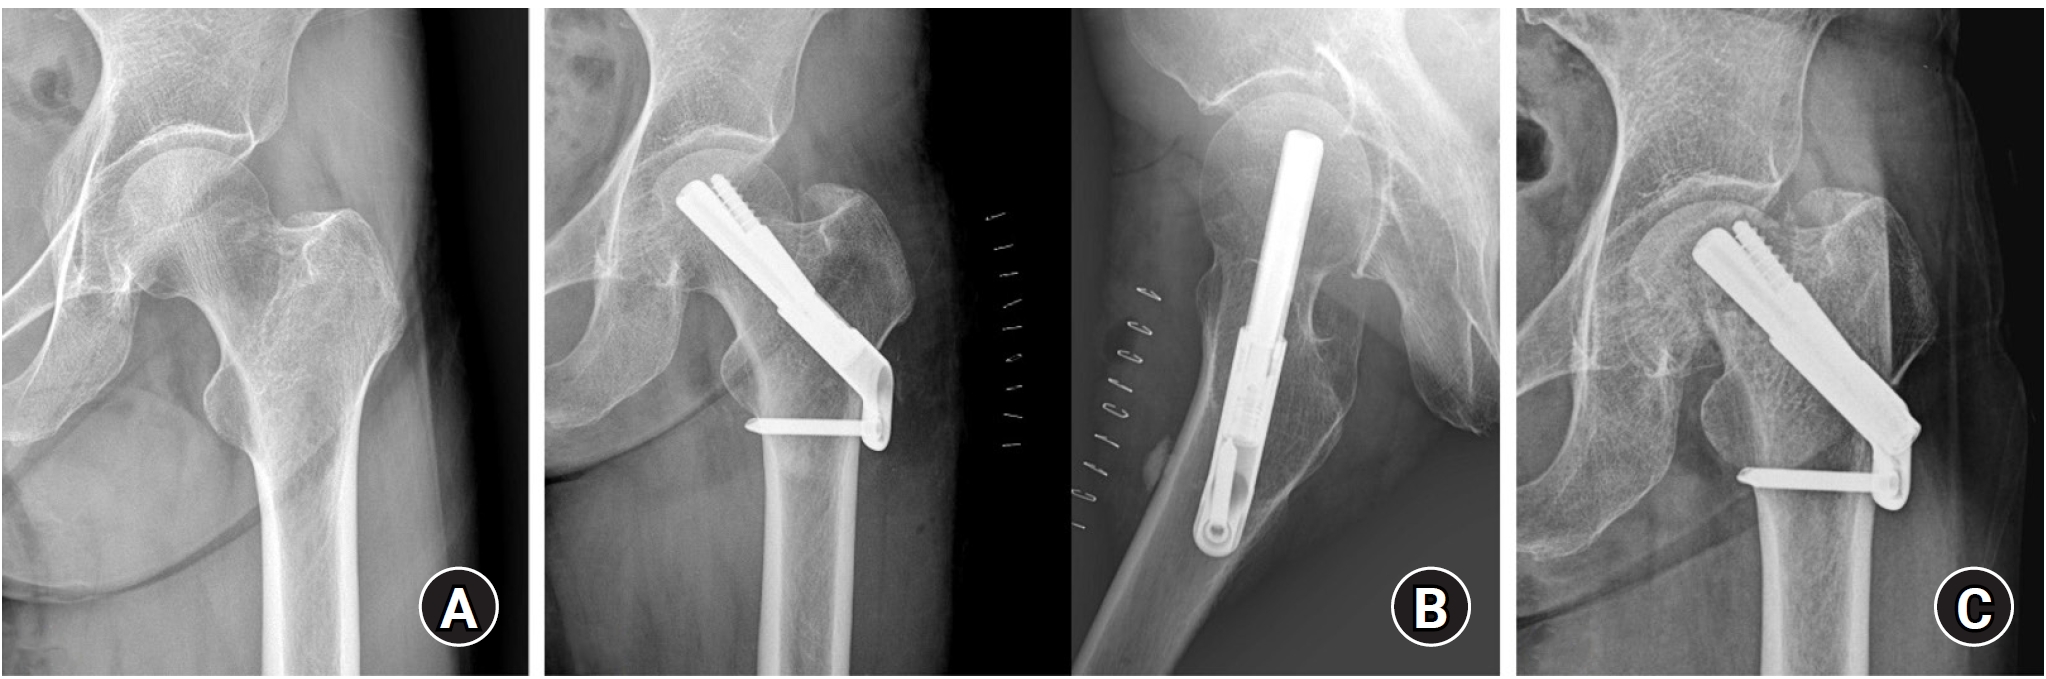

Radiological outcomes

At the final follow-up, the union rate was 87.5% (21/24) in the FNS group and 95.8% (23/24) in the DHS group, with no statistically significant difference between the two groups (P=0.296) (Figs. 2, 3). The mean femoral neck shortening was measured at 6.1 mm in the FNS group and 5.9 mm in the DHS group, and no significant difference was observed (P=0.427).

Fig. 3.

(A, B) An 86-year-old female patient with a stable right femoral neck fracture treated with a dynamic hip system. (C) Postoperative 1-year anteroposterior and axial radiographs show a well-healed fracture site and no complications related to the implant.

Fig. 3. (A, B) An 86-year-old female patient with a stable right femoral neck fracture treated with a dynamic hip system. (C) Postoperative 1-year anteroposterior and axial radiographs show a well-healed fracture site and no complications related to the implant.